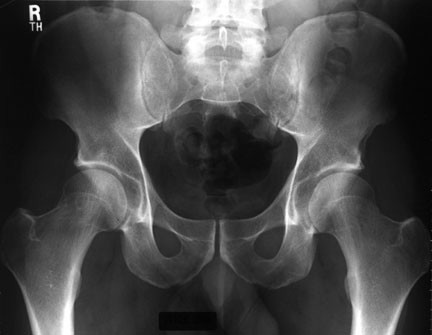

Placa de pelvis normal